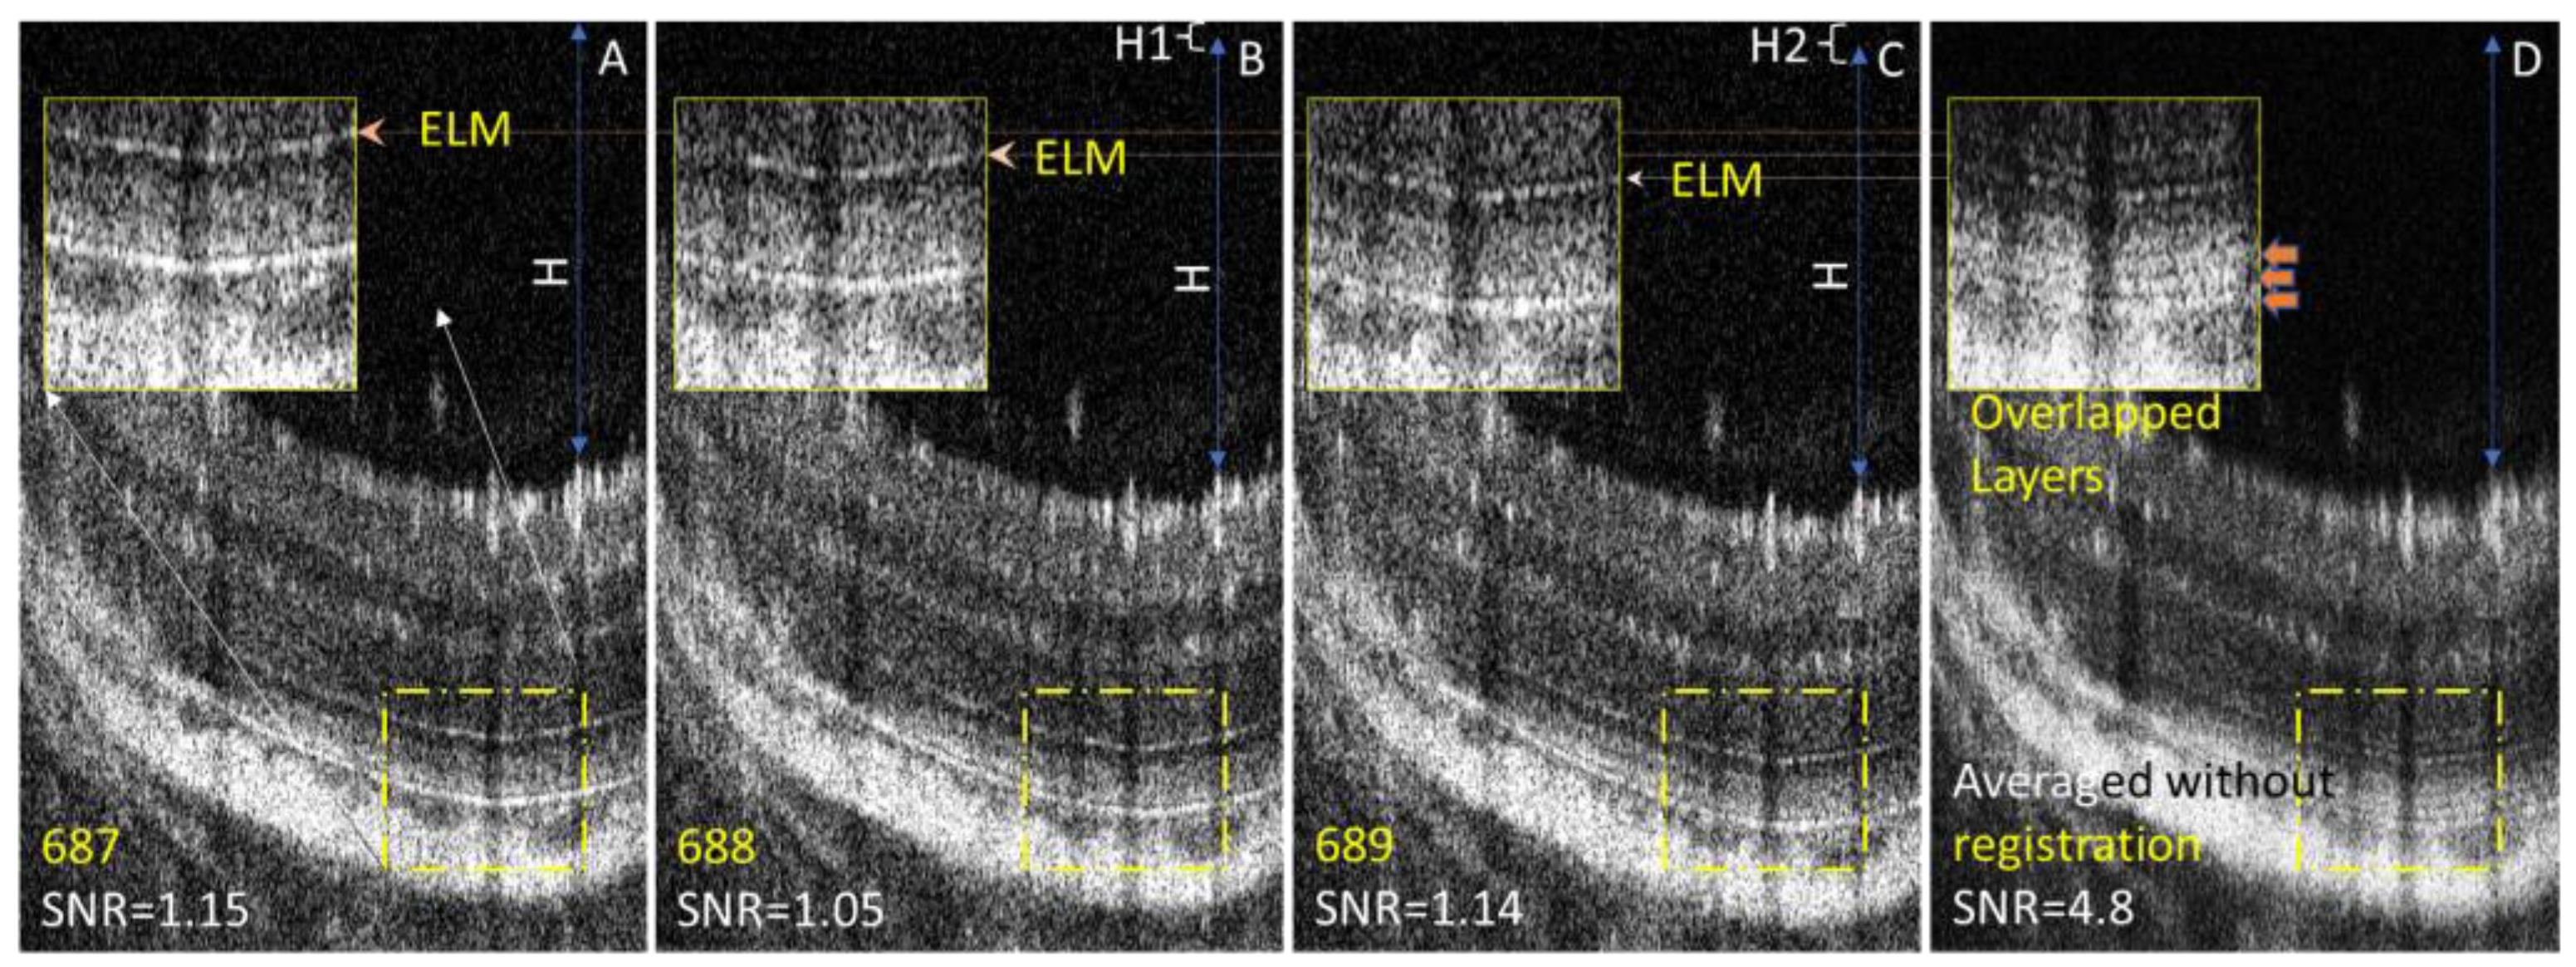

- Hitzenberger, C.K.; Augustin, M.; Wartak, A.; Baumann, B.; Merkle, C.W.; Pircher, M.; Leitgeb, R.A. Signal Averaging Improves Signal-to-Noise in OCT Images: But Which Approach Works Best, and When? Biomed. Opt. Express 2019, 10, 5755–5775. [Google Scholar] [CrossRef]